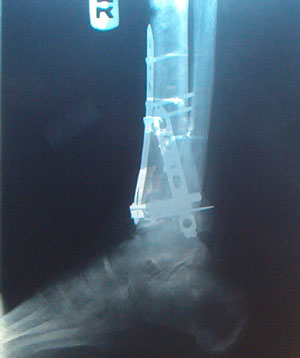

Pictures taken 12/22/2006

You ask yourself, how do you get someone to try and walk with such an injury?